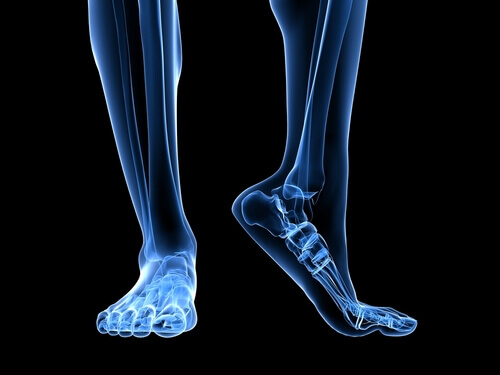

Плантарний фасциїт – це запальний процес у підошовному апоневрозі стопи. Підошовний апоневроз – це сполучна тканина, яка з’єднує п’яткову кістку з проксимальними (основними) фалангами. Ця частина тіла має здатність розтягуватися та стискатися під час ходьби, наче гумова стрічка.

Підошовний апоневроз є широким та товстим, адже йому доводиться витримувати величезний тиск та носити на собі вагу людини.

Анатомія ступні

Є кілька особливостей анатомічної структури нижніх кінцівок, які впливають на силу навантаження підошовного апоневрозу.

Інша важлива особливість анатомічної структури ступні – це характер доторкання ноги до земної поверхні при ходьбі. Люди, які страждають на плоскостопість або викривлення ступні під час руху змушують апоневроз більше напружуватися. Оскільки сила тиску на сполучну тканину збільшується, ризик травмування та розриву апоневрозу зростає у кілька разів.